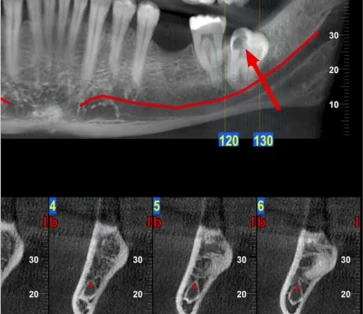

עקירה חלקית של שן בינה כלואה. קיטום של שן בינה הוא הטיפול המומלץ לשיני בינה הממוקמות בקרבה לעצב הלסת ו/או עוטפות את העצב. -

צילום שיני בינה

ישנם מגוון צילומי שיניים המשמשים לעזר בטיפולי שיניים, אולם לא כולם מתאימים להערכה של שיני בינה. צילומי נשך, צילום פנורמי ועוד. -